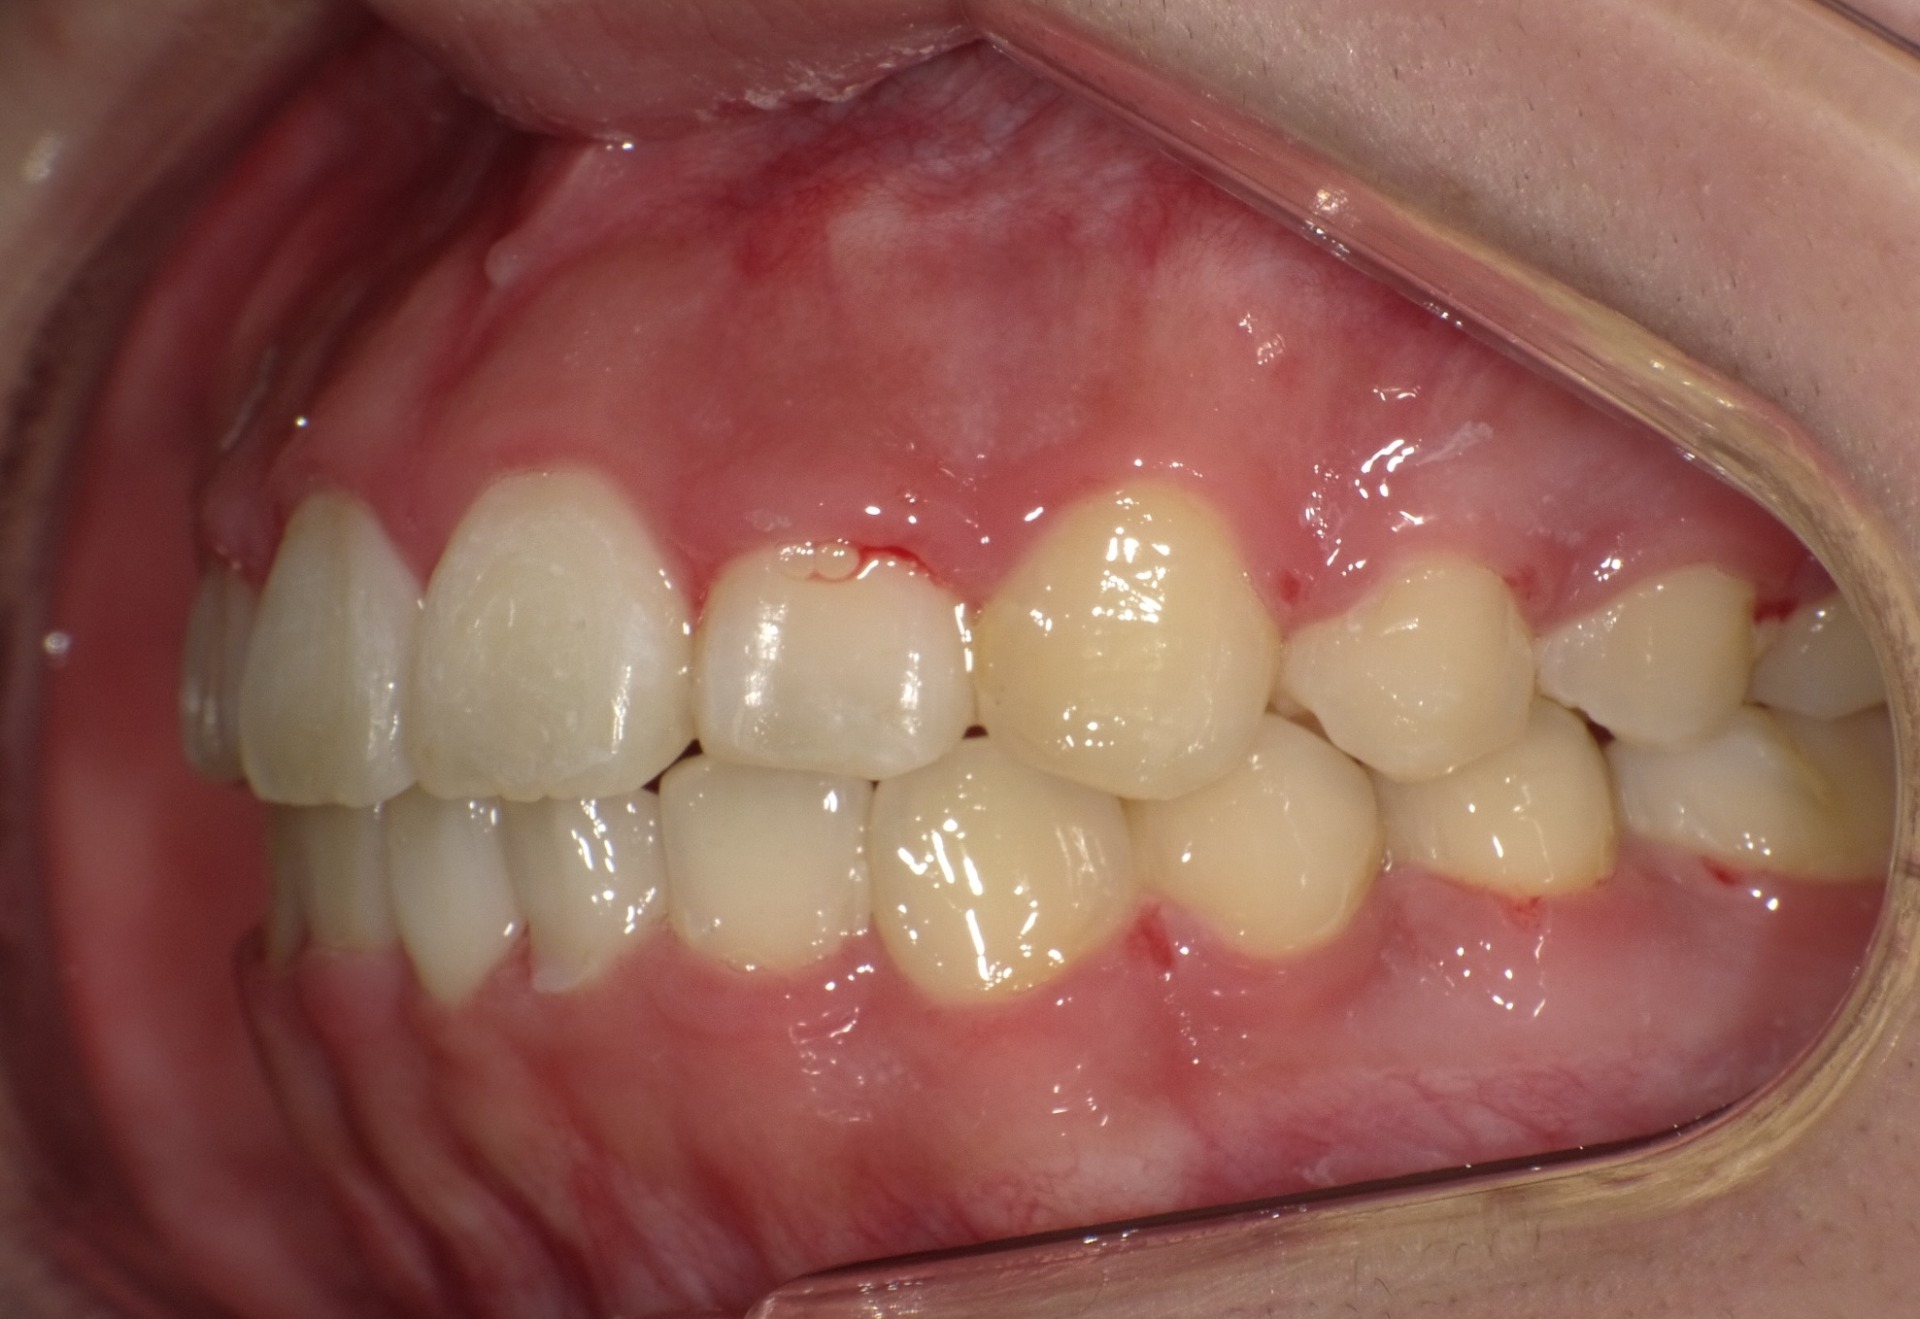

矯正後

| 処置内容 | バイトブロック・プレート拡大処置・ディスタライザー・インビザライン・オーソテイン・マルチブラケット装置・プリフィニッシャー |

| デメリット・院長コメント | 永久歯を抜かない治療のデメリットは、治療期間が長いことです。 ただし、その後の人生の長さを考えると、健全な小臼歯を2本または4本抜歯の矯正治療よりも、はるかにメリットがあるといえます。 また、アーチが小さくならないので、舌が後ろに押し込まれないためいびき防止につながり睡眠の質の向上にもつながります。 |